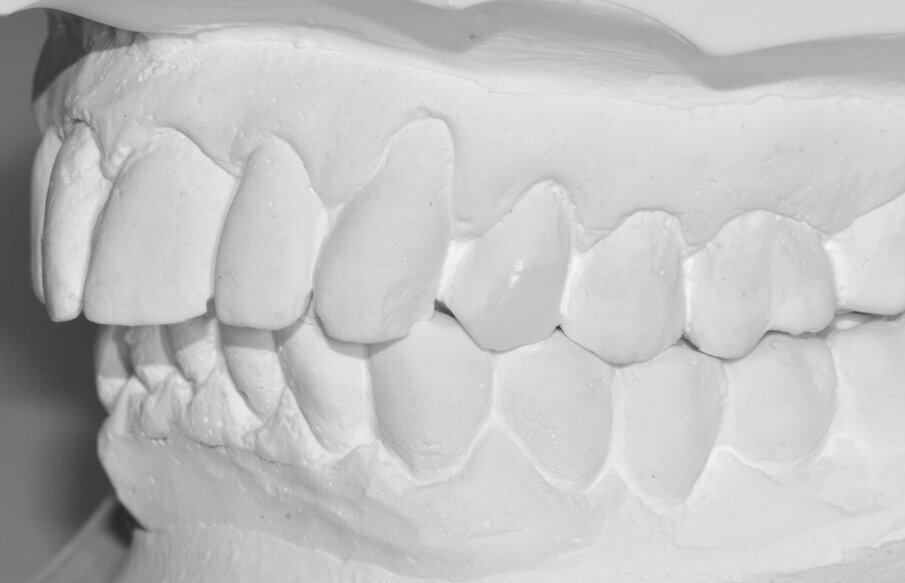

Riguardo al comparto intraorale, dalle radiografie diagnostiche e dall’esame parodontale e occlusale sono emersi aspetti che meritavano una correzione anche nei settori posteriori, ma la paziente ha deciso di effettuare inizialmente il trattamento dei soli gruppi frontali superiore e inferiore demandando a un momento successivo le problematiche dei quadranti posteriori (Figg. 2-6). Nel gruppo frontale superiore si possono notare recessioni gengivali sugli incisivi centrali, che sono anche molto ruotati, e sul canino di sinistra; corone in metallo-ceramica sugli incisivi laterali con esposizione del bordino metallico e una corona in ceramica metal-free sul canino di destra. Inoltre è molto evidente lo squilibrio delle parabole gengivali tra i due canini, per cui per ristabilire un’estetica ottimale sarà necessario anche interessare i tessuti molli eseguendo una chirurgia resettiva sul canino di destra e, al contrario, un lembo a posizionamento coronale sul canino di sinistra (Fig. 7).

Da un punto di vista protesico verranno eseguite corone singole in zirconia stratificata sugli elementi 13-12-11-21-22 e una faccetta in disilicato di litio sul 23. A causa della notevole rotazione dei due incisivi centrali in fase di ceratura abbiamo optato per due corone complete anziché due faccette per una migliore distribuzione degli spazi protesici dei quattro incisivi (Fig. 8). Il gruppo frontale inferiore invece verrà protesizzato con corone in zirconia stratificata sugli elementi 32-31-41-42-43 splintate per compensare una mobilità di grado 1 dei quattro incisivi.